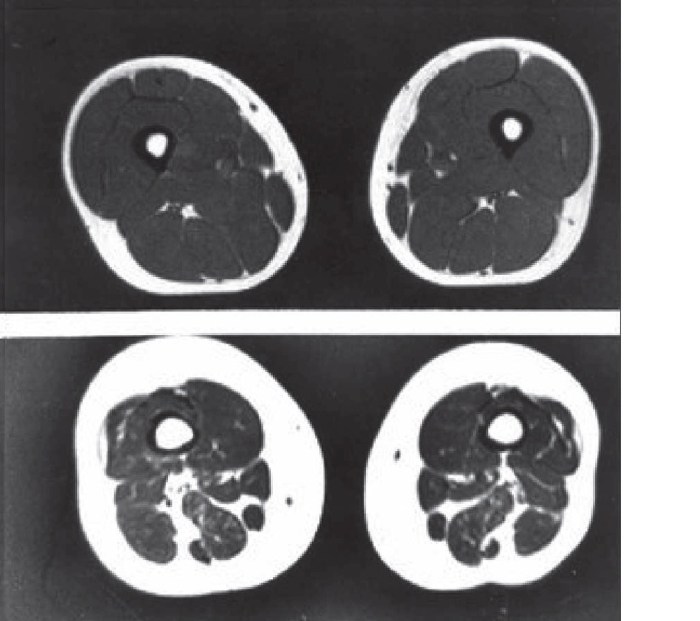

However, a more serious condition has been seen in people who stay the same weight but start noticing unfavorable physical conditions. This is called, Sarcopenic obesity. Sarcopenic obesity is the mix of two different terms. Sarcopenia is the process of muscle wastage and of course obesity is excessive body fat levels.

Sarcopenia obesity is a lot worse than carrying visceral fat in that the risk of getting metabolic syndrome disease is higher. Hypertension is 2.3 times higher and diabetes is 19 times higher than normal people. (4) Similar to visceral fat, people who have sarcopenia obesity don’t show any changes on the scale.

After reaching to age of 25, you start losing muscle mass 0.5-1% per year, then 1-1.5% after the age of 40. The lost muscle is replaced with fat, and then people become sarcopenia obesity, which are found in skinny fat person. (5)